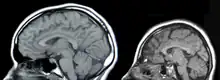

Microcephaly (from Neo-Latin microcephalia, from Ancient Greek μικρός mikrós "small" and κεφαλή kephalé "head"[2]) is a medical condition involving a smaller-than-normal head.[3] Microcephaly may be present at birth or it may develop in the first few years of life.[3] Brain development is often affected; people with this disorder often have an intellectual disability, poor motor function, poor speech, abnormal facial features, seizures and dwarfism.[3]

The disorder is caused by a disruption to the genetic processes that form the brain early in pregnancy,[3] though the cause is not identified in most cases.[4] Many genetic syndromes can result in microcephaly, including chromosomal and single-gene conditions, though almost always in combination with other symptoms. Mutations that result solely in microcephaly (primary microcephaly) exist but are less common.[5] External toxins to the embryo, such as alcohol during pregnancy or vertically transmitted infections, can also result in microcephaly.[3] Microcephaly serves as an important neurological indication or warning sign, but no uniformity exists in its definition. It is usually defined as a head circumference (HC) more than two standard deviations below the mean for age and sex.[6][7] Some academics advocate defining it as head circumference more than three standard deviations below the mean for the age and sex.[8]

There is no specific treatment that returns the head size to normal.[3] In general, life expectancy for individuals with microcephaly is reduced, and the prognosis for normal brain function is poor. Occasional cases develop normal intelligence and grow normally (apart from persistently small head circumference).[3][9] It is reported that in the United States, microcephaly occurs in 1 in 800-5,000 births.[4]